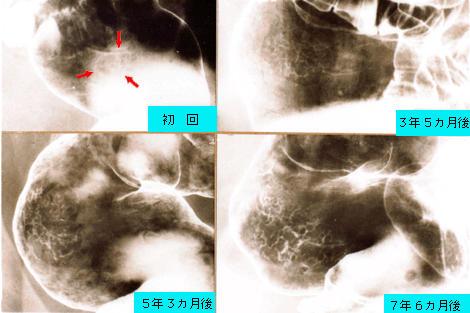

Nodule- aggregating lesion of the rectum in a HNPCC patient and it's natural history based on a radiographic analysis.

Tokyo Pref., Cooperative study between National Cancer Center and Kyushu Cancer Center

[ Image ID:1558 ]

Location

Large intestine(Colon)/Rectum

Technique, Method

X-ray

Size

35 - 40